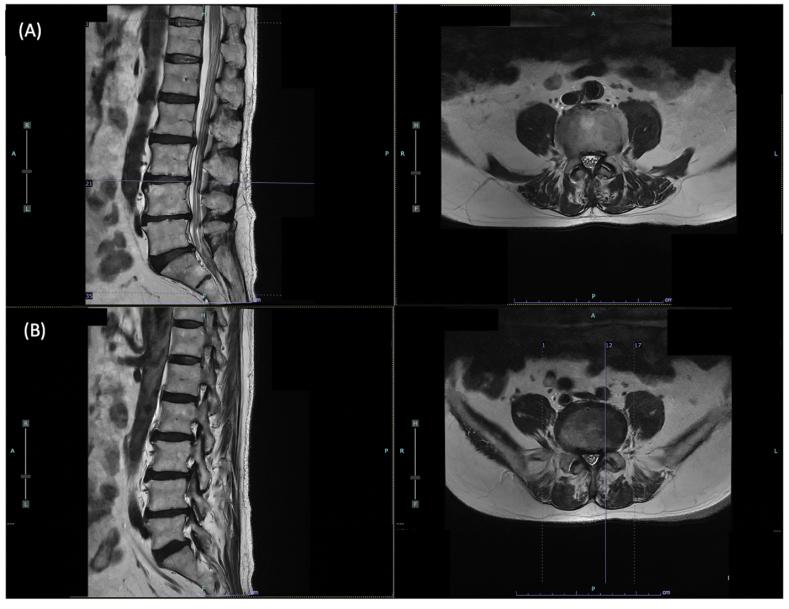

Postherpetic neuralgia mimicking lumbar radiculopathy.

https://cdn.ncbi.nlm.nih.gov/pmc/blobs/067e/11652748/f0b8fe7fd279/gr1.jpg